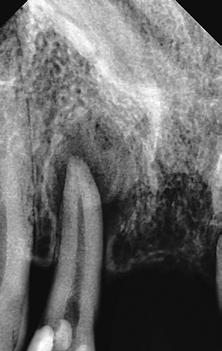

A 10 éves férfi páciens a felső frontfogai késői/nem megvalósuló előtörése miatt kereste fel a rendelőnket. A klinikai és a radiológiai vizsgálat során a jobb felső nagymetszőfog impakcióját észleltük (1. ábra). A fog horizontális tengelyállással és dilacerált gyökérrel rendelkezett. A felső dentális középvonal a fogak vándorlása miatt jelentős mértékben elcsúszott. A bal felső kismetszőfog is rendkívül kedvezőtlen pozícióba került.

Dr. Kazem Dalaie, dr. Samin Ghaffari, dr. Mazir Mir (Irán, Németország) 1. a ábra: Az intraorális felvételen jól látható a jobb felső nagymetszőfog lehetséges impakciójára utaló foghiány.

1. b ábra: A panoráma röntgenfelvételen megfigyelhető a teljes impakcióban lévő jobb felső nagymetszőfog. 1. c ábra: A CBCT felvétel is igazolja a jobb felső nagymetszőfog impakcióját.